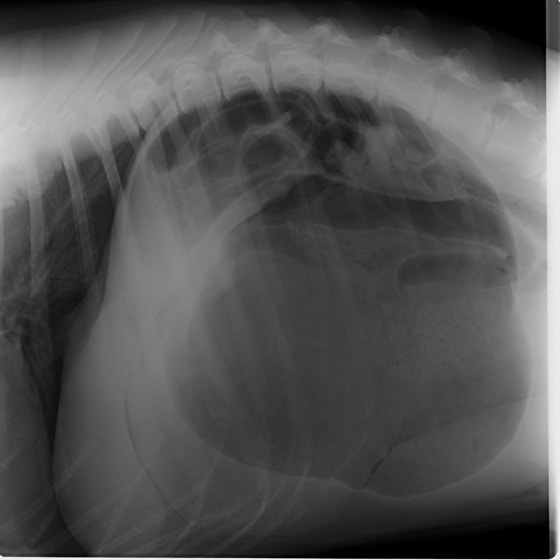

腹部と胸部を隔てている横隔膜が何らかの原因で裂け、腹部臓器(肝臓、小腸、胃など)が胸腔内に脱出してしまう病気です。脱出した臓器による肺・心臓の圧迫や、臓器の機能障害により、様々な呼吸器症状や消化器症状を示します。原因には外傷性と先天性の2つがあり、犬・猫で最も多いのは交通事故による外傷性横隔膜ヘルニアです。犬・猫の室内飼育が一般的になったことで交通事故が減り、それに伴い本疾患に遭遇することも減りましたが、屋外を自由に出入りしている猫では注意が必要です。屋外から帰った猫がお腹で呼吸をしている、苦しそうにしているなど、少しでも症状がある場合には早めに動物病院を受診し、レントゲン検査を受けられることをお勧めいたします。以下に交通事故が原因 と考えられる外傷性横隔膜ヘルニアの猫の症例をご紹介致します。

術前レントゲン

腹部臓器が胸腔内に脱出し、腹部と胸部の境界および心臓や肺の陰影が不明瞭になっています。また、胸腔内に消化管のガス陰影が認められます。

術後レントゲン

腹部臓器が腹腔内に戻り、腹部と胸部の境界および心臓や肺の陰影が明瞭に見えるようになりました。